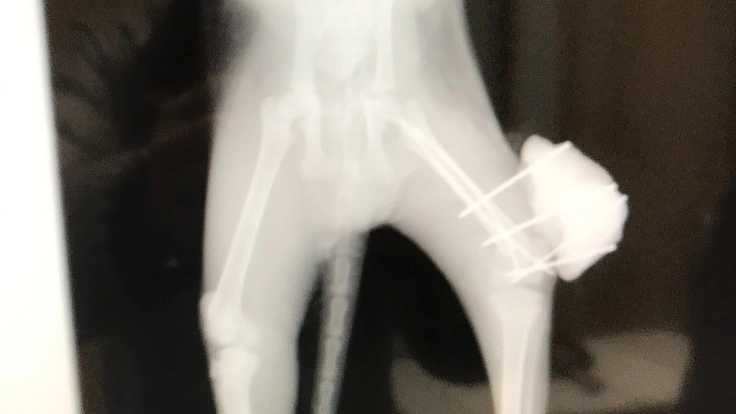

脚の様子がおかしいので動物病院でレントゲンを撮ってもらうと後脚大腿骨が関節のすぐ近くで骨折して膝の皿も剥離して離れていました。

普通でしたら断脚ということでしたが、まだ1100グラムの仔猫ですから難しい手術になっても手術して元通り治して4本の脚で歩き、走り、ジャンプできるようにしてやりたいという思いで動物病院の先生に無理をお願いして手術してもらいました。

交通事故で大腿骨を骨折していた1100グラムの仔猫。

通常でしたら断脚ですが、4本の脚で歩き、走り、ジャンプできるよう手術を受けさせます。

(既に手術は完了して現在は入院治療中です)

動物病院のスケジュールにより定期的にレントゲン撮影して骨折部分のつながり状況をみてギプスを外して治療を続けます。

治療・手術内容 左後脚大腿骨骨折手術